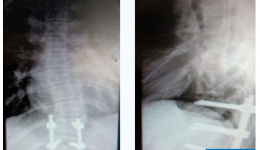

“当初果断选择做手术的决定是正确的!感谢省医昌耘冰教授团队以及茂医脊柱外科一区医护团队的共同帮助,治好了我的脊髓型颈椎病......”在茂名市人民医院脊柱外科病房内,53岁的林伯(化名)开心地向医护人员致谢。近日,在广东省人民医院(以下简...

发布时间:2024-09-23|来自:全栏目管理员